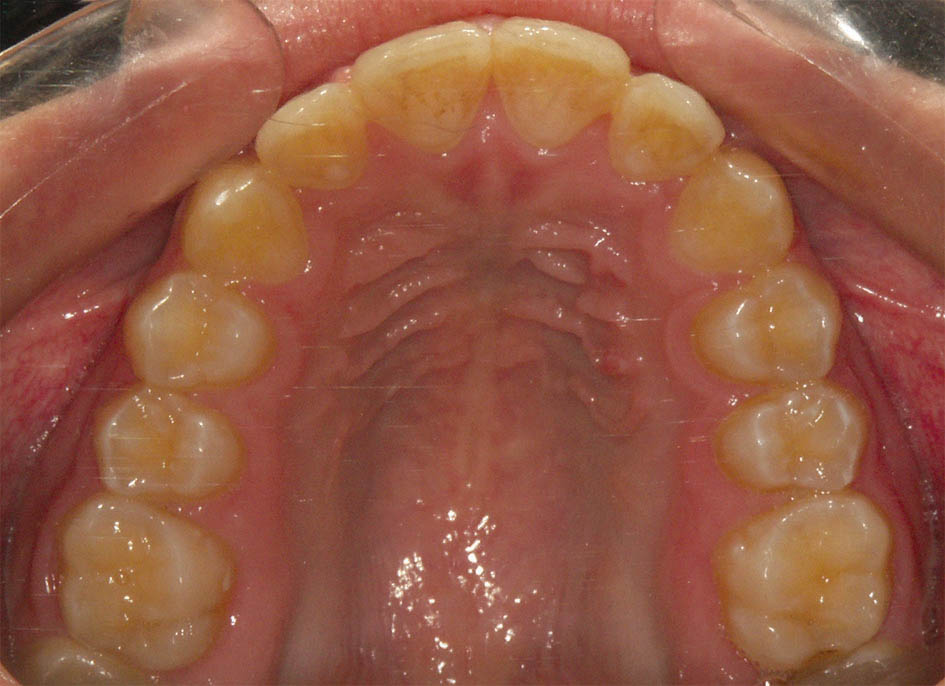

شکل 66-3 : قوس بالا در ابتدای درمان